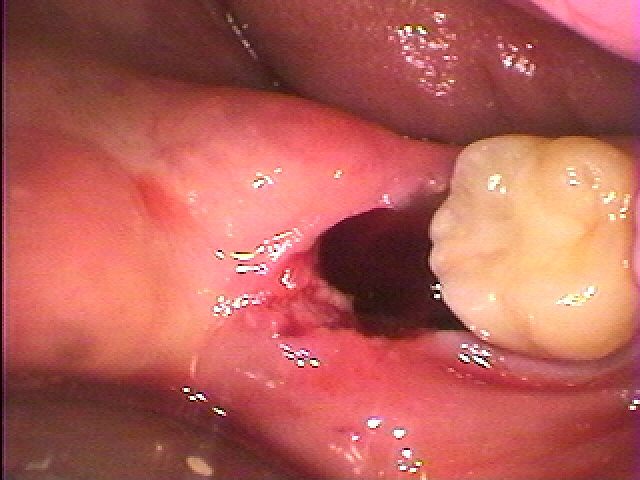

このように大きく湾曲していました

抜けにくい親知らずでした

このように大きく湾曲していました

抜けにくい親知らずでした